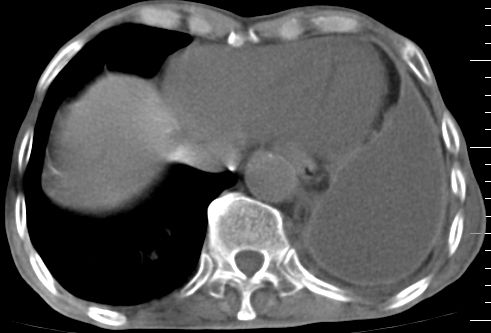

标题: CT10141:男、84岁,咳嗽、咯血1年。 [打印本页]

标题: CT10141:男、84岁,咳嗽、咯血1年。

支持左侧中央型肺癌伴下叶肺不张\\纵隔淋巴结转移.左侧包裹性胸腔积液\\心包积液.左侧少量胸腔积液..慢性支气管炎伴部分间质纤维化.

支持:左侧中央型肺癌伴下叶肺不张\\纵隔淋巴结转移.左侧包裹性胸腔积液\\心包积液.左侧少量胸腔积液..慢性支气管炎伴部分间质纤维化.另:支气管分支根部明显阻塞 狭窄,内膜凸凹不平,提示内膜增生物。

咯血病史较长,左肺下叶实变,体积未明显缩小,隐约可见血管影及坏死阴影,双肺门及纵隔淋巴结增大,心包增厚积液,纵隔右移位,单侧胸腔积液,首先考虑:大叶型肺泡癌伴纵隔心包转移。